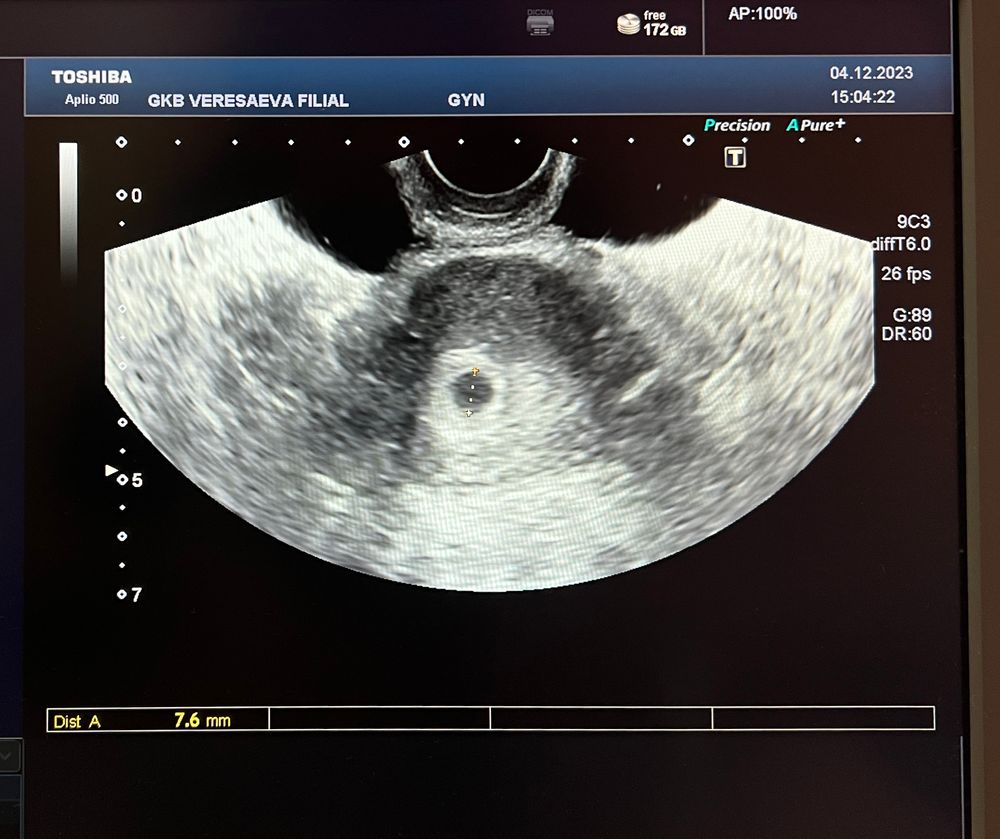

Надежда в Зачатие 2 года Ну и хорошо Добралась до врача, сделала узи ПЯ в матке, срок ~5 недель, все как я и насчитала. Но сердечко еще не слышно, через 2 недели снова на узи. Но уже спокойно все на месте и развивается. Надеюсь все будет как надо🤞🏼 Посмотрите еще 20 записей на эту тему Лучший ответ Тру вумен Удачи 🤞🏻 05.12.2023 Ответить Надежда Тру вумен, спасибо! 05.12.2023 Ответить Отменить Ответить Эви тест реагентит? Биохимическая беременность Чаты Беременных Выберите чат: Январята-2026 Февралята-2026 Мартята-2026 Апрелята-2026 Майчата-2026 Июнята-2026 Июлята-2026 Августята-2026